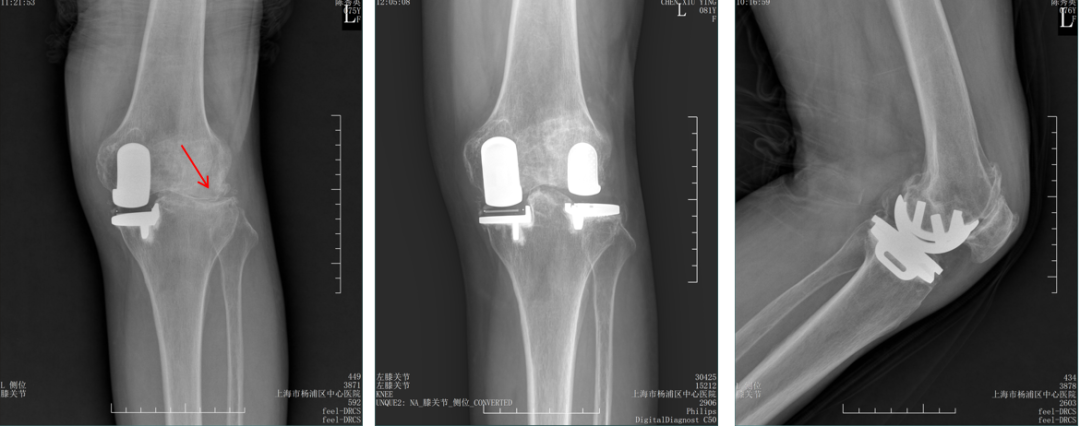

胫骨假体内侧悬挂

AP位胫骨假体位置:胫骨假体内侧悬挂>2mm。

股骨假体偏内放置

AP位胫骨与股骨假体位置:股骨假体轻度内翻,中轴线与胫骨假体中线不一致,偏内侧。

胫骨假体偏大,且后倾不足

侧位胫骨假体位置:胫骨假体后侧悬挂>2mm,后倾2°。

胫骨假体后倾角度大

侧位片胫骨假体位置:胫骨假体后倾12°,前后缘齐平 。